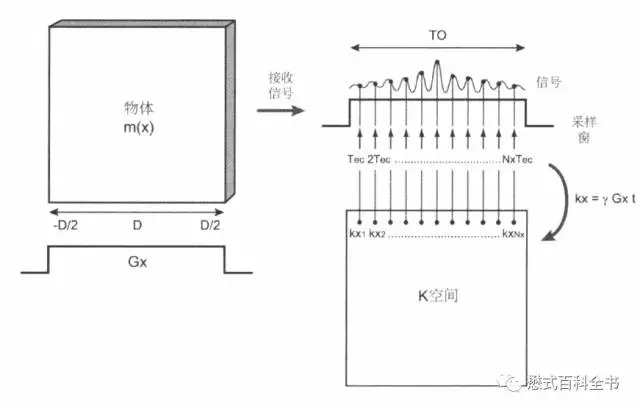

图3:上图是一个K-space的示意图

上图是一个K空间的示意图,我们知道磁共振需要需要对质子进行空间定位,会用到不同方向的梯度磁场。

如果以一个2D采集为例,首先通过层面选择梯度,激发某一固定的一层,然后在通过相位偏码梯度和频率编码梯度来对该层的质子进行空间定位。

一个二维平面,我们可以把它分为两个正交方向,即:Ky(相位编码方向)和Kx(频率编码方向)。一个TR周期,把采集的一次信号填充到K空间中,在相位编码方向上,有多少个步级,我们就需要填充多少个相位编码线,最后把K空间数据填充完毕,进行图像后处理形成磁共振图像。

图4:频率编码梯度在采集接收信号的时候持续地施加,信号采样持续时间为Ts(图中为TO),频率编码梯度也持续到该过程结束。

在MR图像采集过程中,每填充一条相位编码线,相位编码梯度都发生变化,而频率编码梯度并不变。

相位编码梯度变化一次,进行质子的相位编码方向(Ky)的定位。在频率编码方向上,一次信号采集,会采集很多的采样点,作为频率编码方向(Kx)的定位。